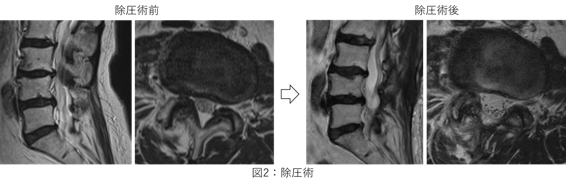

上記の症状(間欠跛行)が目立つ際には腰部脊柱管狭窄症などを鑑別に挙げます。MRIにて脊髄が通るトンネルである脊柱管が狭くなっていることでこの脊髄が圧迫されていることを確認します(下図1)。

投薬などを行うも症状が強く残る場合には手術を考えます。脊髄の圧迫の原因となっている脊椎の一部分を切除したり、肥厚した黄色靭帯を切除したりすることによって脊髄の圧迫を解除します(下図2)。これによって脊髄の自力回復を促し、現在の下肢症状の改善を狙います。症例によって2cmほどの小さな皮切で行える内視鏡手術を選択するか、通常通り3~4cm程の皮切を設けてしっかりと患部を同定して行う手術を選択するかを考えております。術後2週ほどで退院される患者さんが多いですが、さらにリハビリが必要な場合には近隣の病院と連携し、さらにじっくりリハビリが受けられる環境を用意しております。